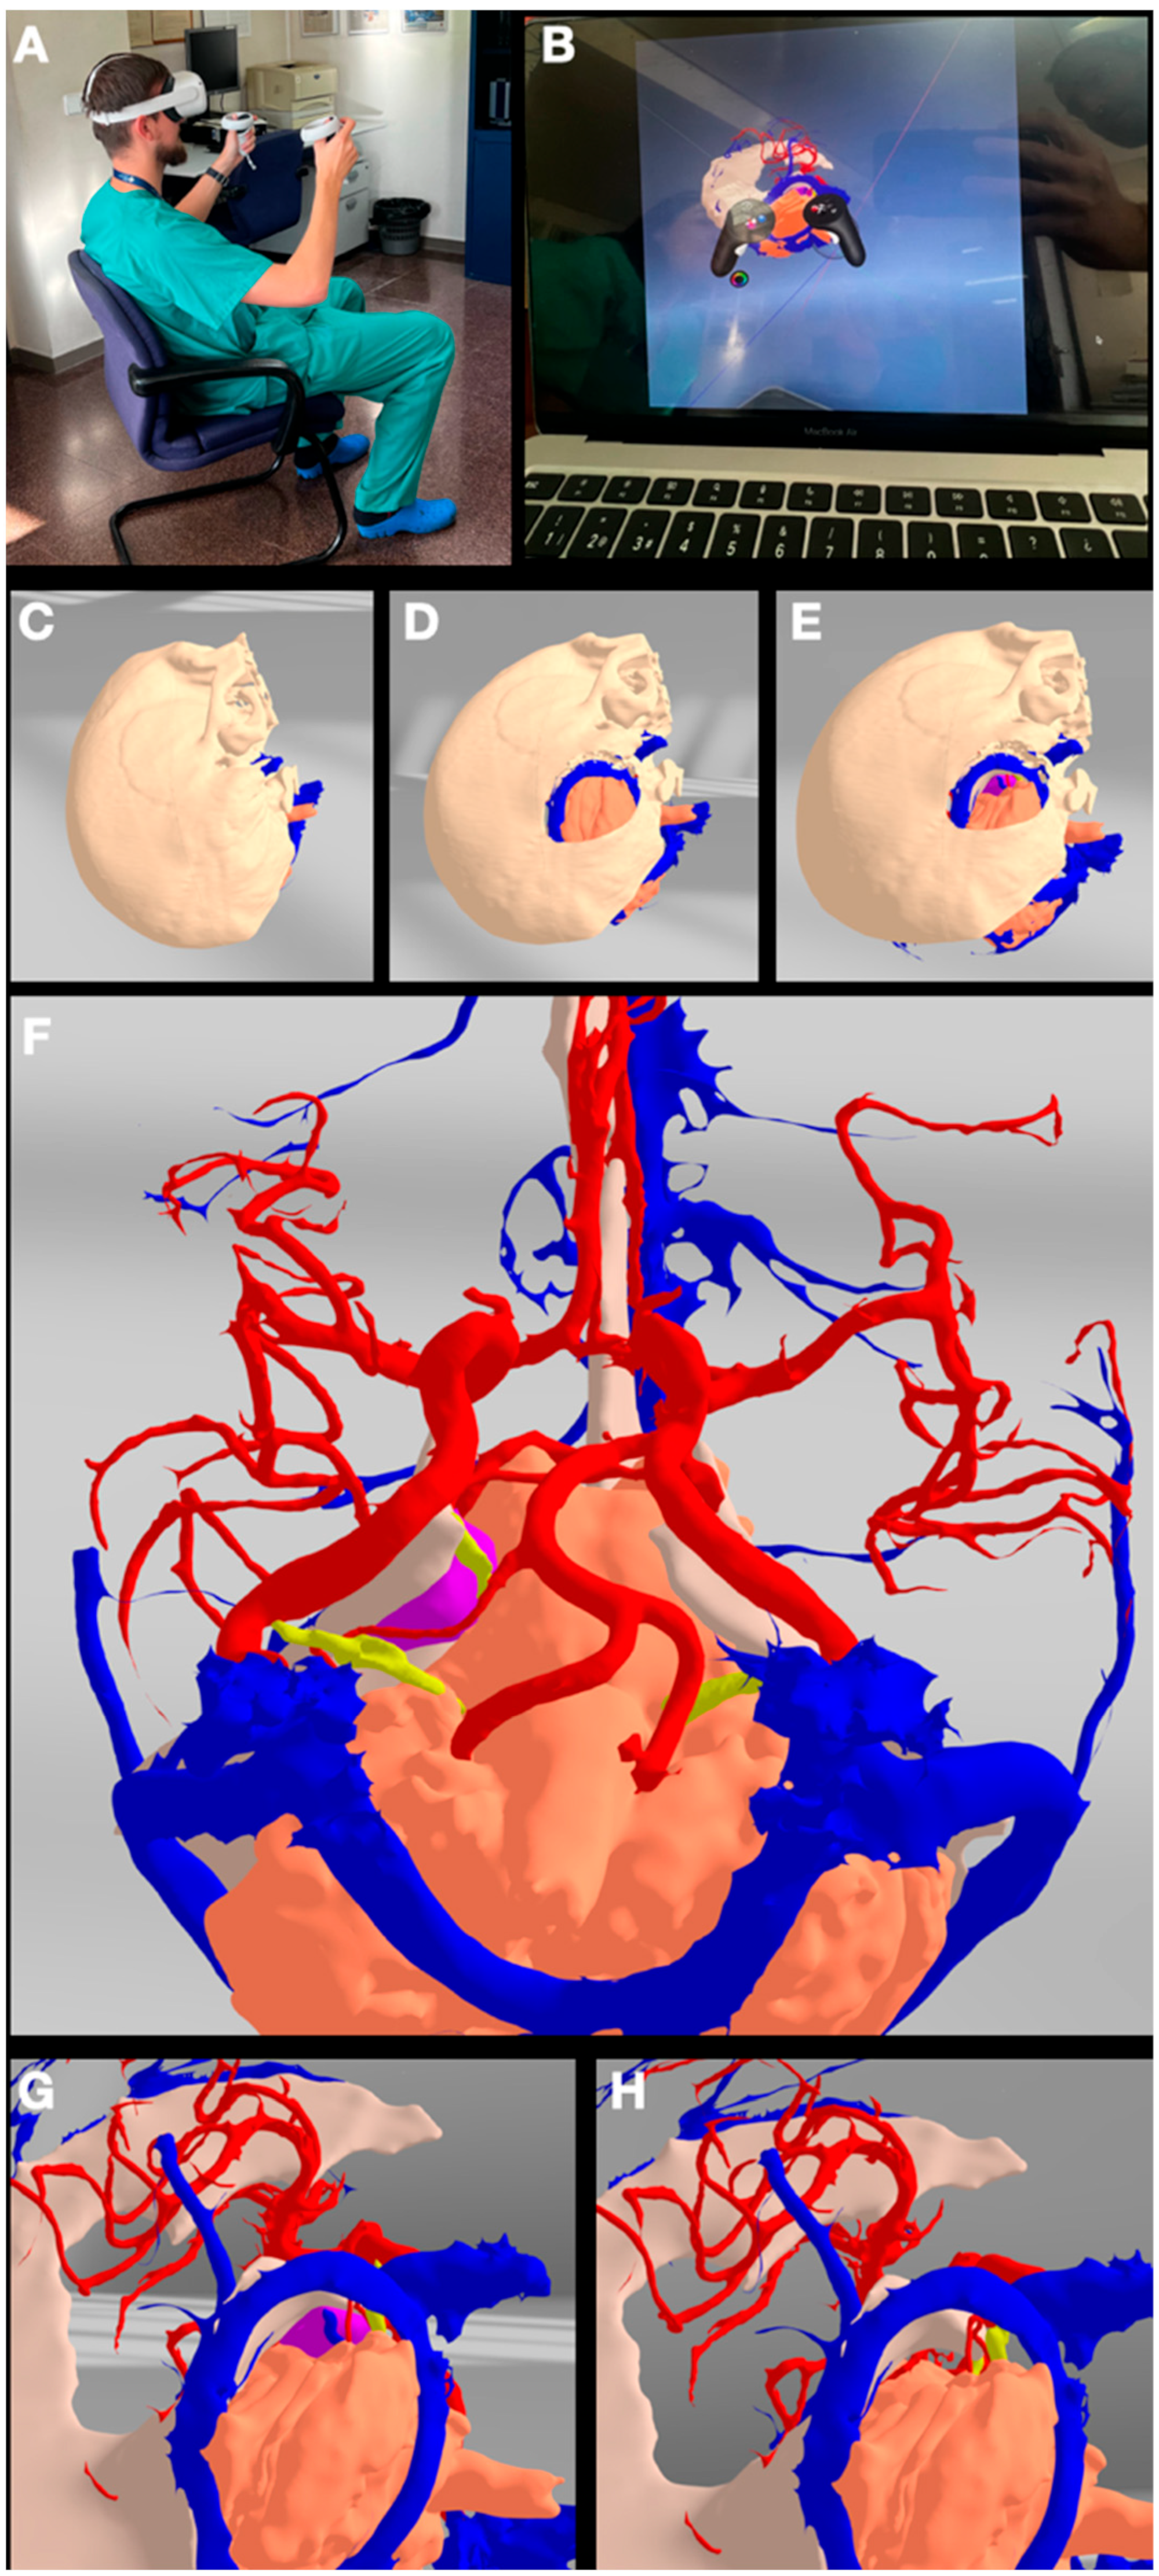

4.2. Virtual Reality